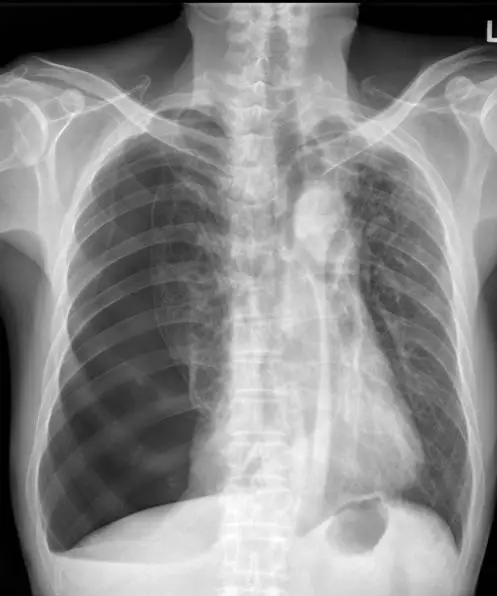

61 歲男性突發性的胸痛、呼吸困難,其胸部 X光如圖示,最主要的診斷為何?

本題胸部 X 光(後前位,PA view)呈現以下關鍵影像發現:

- 左側臟層肋膜線(visceral pleural line)清晰可見:在左肺外側可見一條銳利的細線,為塌陷肺組織的邊界,為氣胸的最重要診斷依據。

- 胸膜線外側肺紋消失:胸膜線以外(靠近胸壁側)呈現異常高度透亮區域,完全無血管紋路(absent lung markings),此為氣胸的典型表現——空氣積聚於肋膜腔內。

- 左肺部分萎縮(lung collapse):左側肺實質向肺門方向收縮,肺容積明顯縮小。

- 縱膈輕度向右偏移(mediastinal shift):氣胸側壓力升高可推擠縱膈向對側移位,此時需警惕張力性氣胸(tension pneumothorax)的可能。

- 右側肺野正常:右側肺紋路清晰,無浸潤、氣胸或特殊異常。

影像結論:上述表現高度符合左側自發性或繼